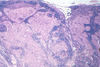

What are the **microscopic features **of ILC?

- Small cells

- Single file pattern

- Targetoid growth pattern

- No gland formation

- Intracytoplasmic mucin vacuoles

- Signet ring cells